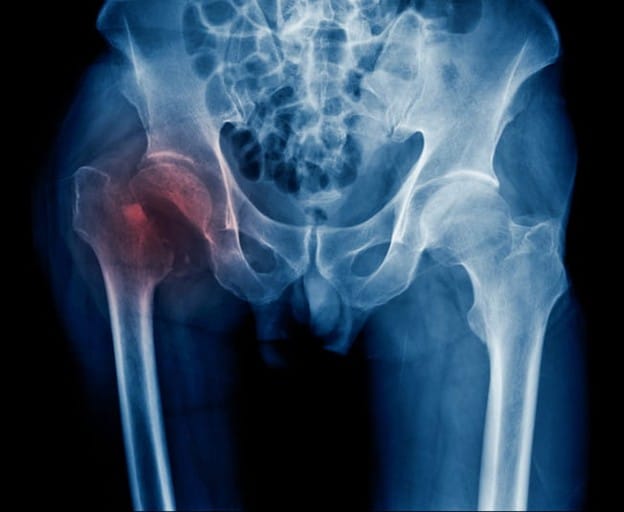

According to the Cleveland Clinic, a broken hip is when the upper part of the thigh bone (femur) breaks apart from the hip joint. Breaking your hip is a serious injury that usually requires surgery to be fixed.

At the hospital, you will be given a physical exam and a medical scan, such as an X-ray, CT scan, or MRI, to assess the extent of the damage. The doctors will discuss your options with you for treatment. In most cases, surgery will be required to repair the break. Seniors without a caregiver at home will need to stay in a skilled nursing facility for short-term rehabilitation care during recovery.